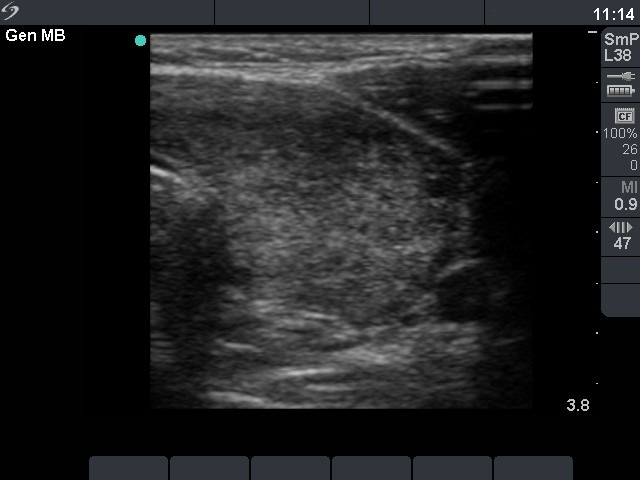

Left lobe, transverse scan. Around 50% of the thyroid is hypoechogenic.

Right lobe, horizontal view